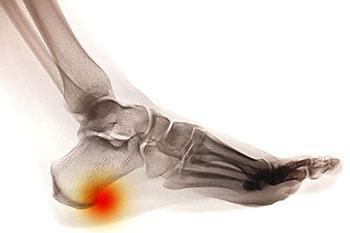

Orthotics, unlike typical shoe inserts, are prescribed by a podiatrist to help provide your feet with cushion and support. They can also aid in correcting a specific foot condition that you may be dealing with. Conditions such as diabetes, plantar fasciitis, bursitis,...